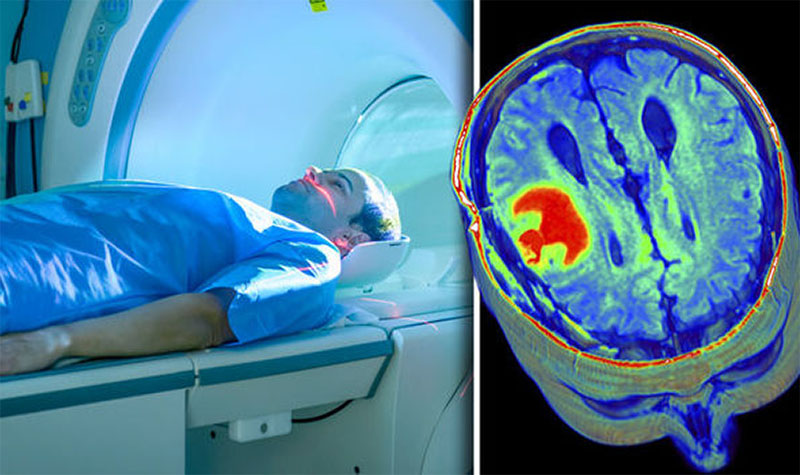

Медицинская диагностика: КТ и МРТ головного мозга

Раздел: Пульс времени